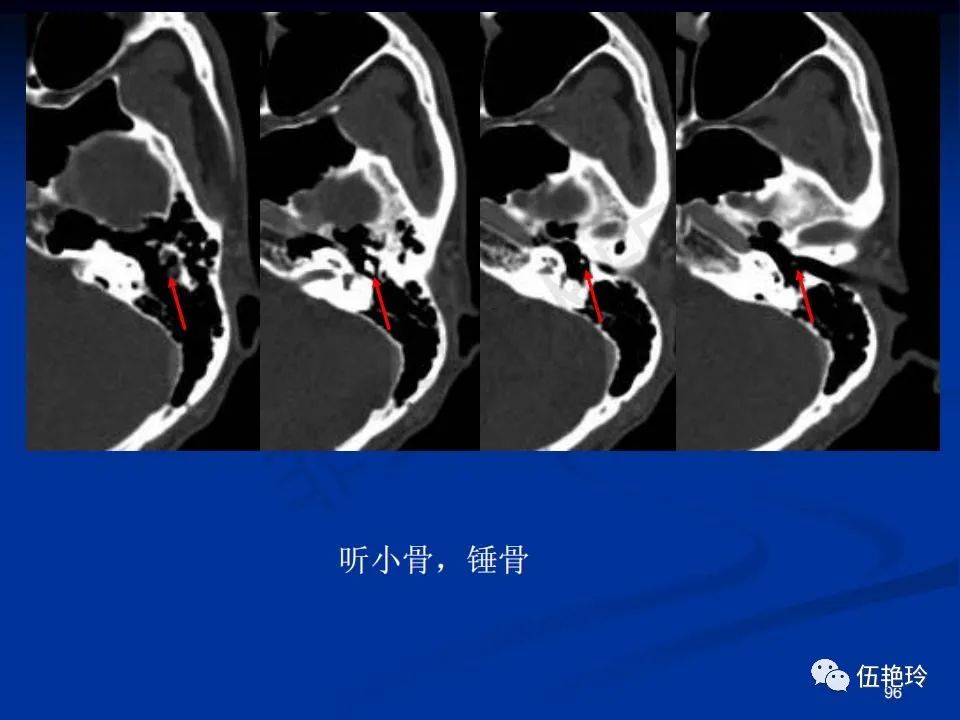

耳与面神经的解剖